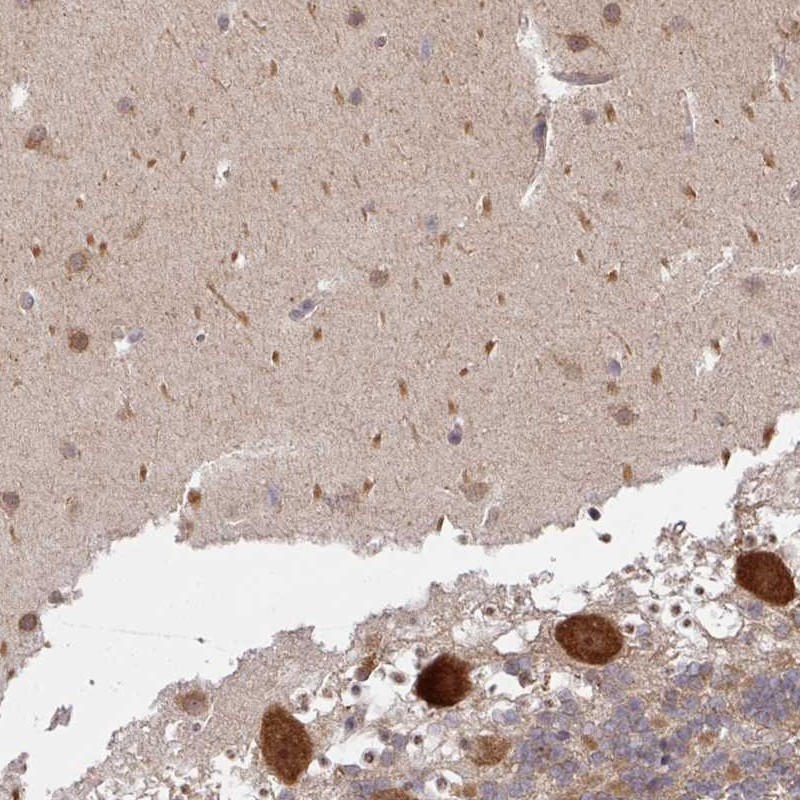

Immunohistochemical staining of human cerebellum shows cytoplasmic and nuclear positivity in Purkinje cells.